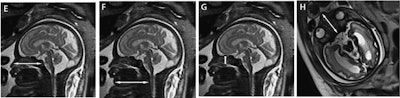

The retrospective study included 1.5-tesla MRI scans (Optima, GE Healthcare) from 255 women whose fetuses' brains were imaged from the 24th to 36th week of gestation. Participants were chosen because the fetus appeared normal on first-trimester ultrasound, had a normal facial morphology for gestational age on MRI, and had no intra- and/or extracranial abnormalities. The women were also undergoing MRI scans due to the suspicion of fetal infection, a cerebral abnormality on ultrasound, and reduced fetal movement.

The researchers targeted eight facial features that are considered critical in the normal development of the fetal face and can be easily measured on prenatal MRI. They also can be correlated with gestational age and gender. In this study, the researchers confirmed 134 male and 88 female fetuses.